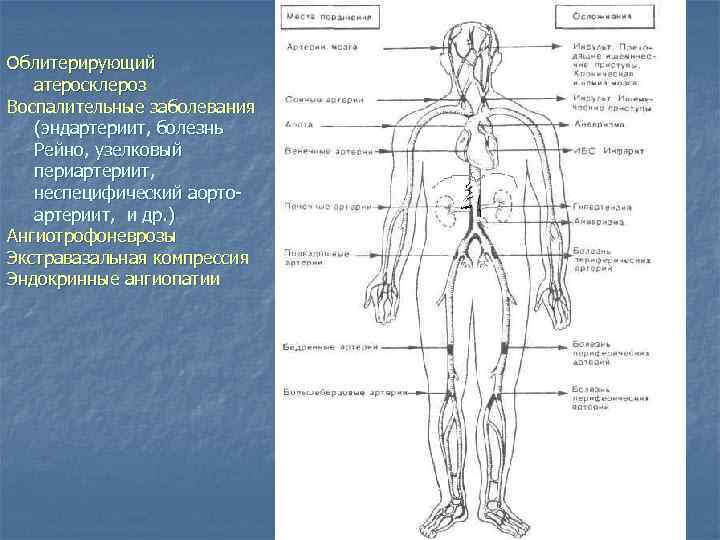

Хроническая артериальная недостаточность 1) 2) 3) 4) 5) Облитерирующий атеросклероз Воспалительные заболевания (эндартериит, болезнь Рейно узелковый периартериит, неспецифический аортоартериит, и др. ) Ангиотрофоневрозы Экстравазальная компрессия Эндокринные ангиопатии Острая артериальная недостаточность 1) Эмболии 2) Тромбозы 3) Травмы артерий

Облитерирующий атеросклероз Воспалительные заболевания (эндартериит, болезнь Рейно, узелковый периартериит, неспецифический аортоартериит, и др. ) Ангиотрофоневрозы Экстравазальная компрессия Эндокринные ангиопатии